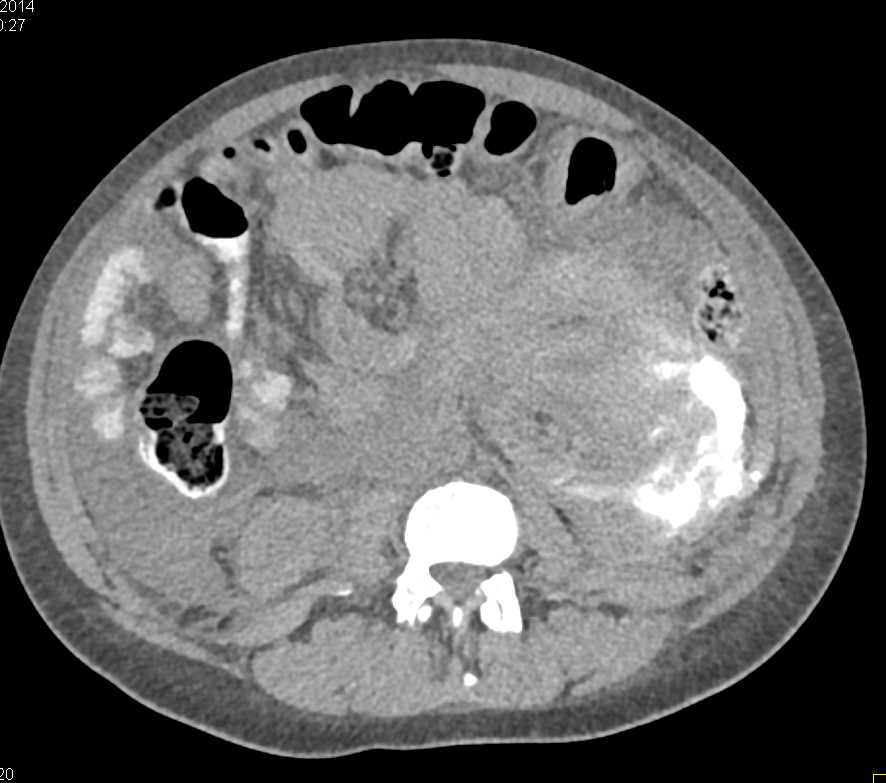

Right Renal Artery and Splenic Artery Aneurysms